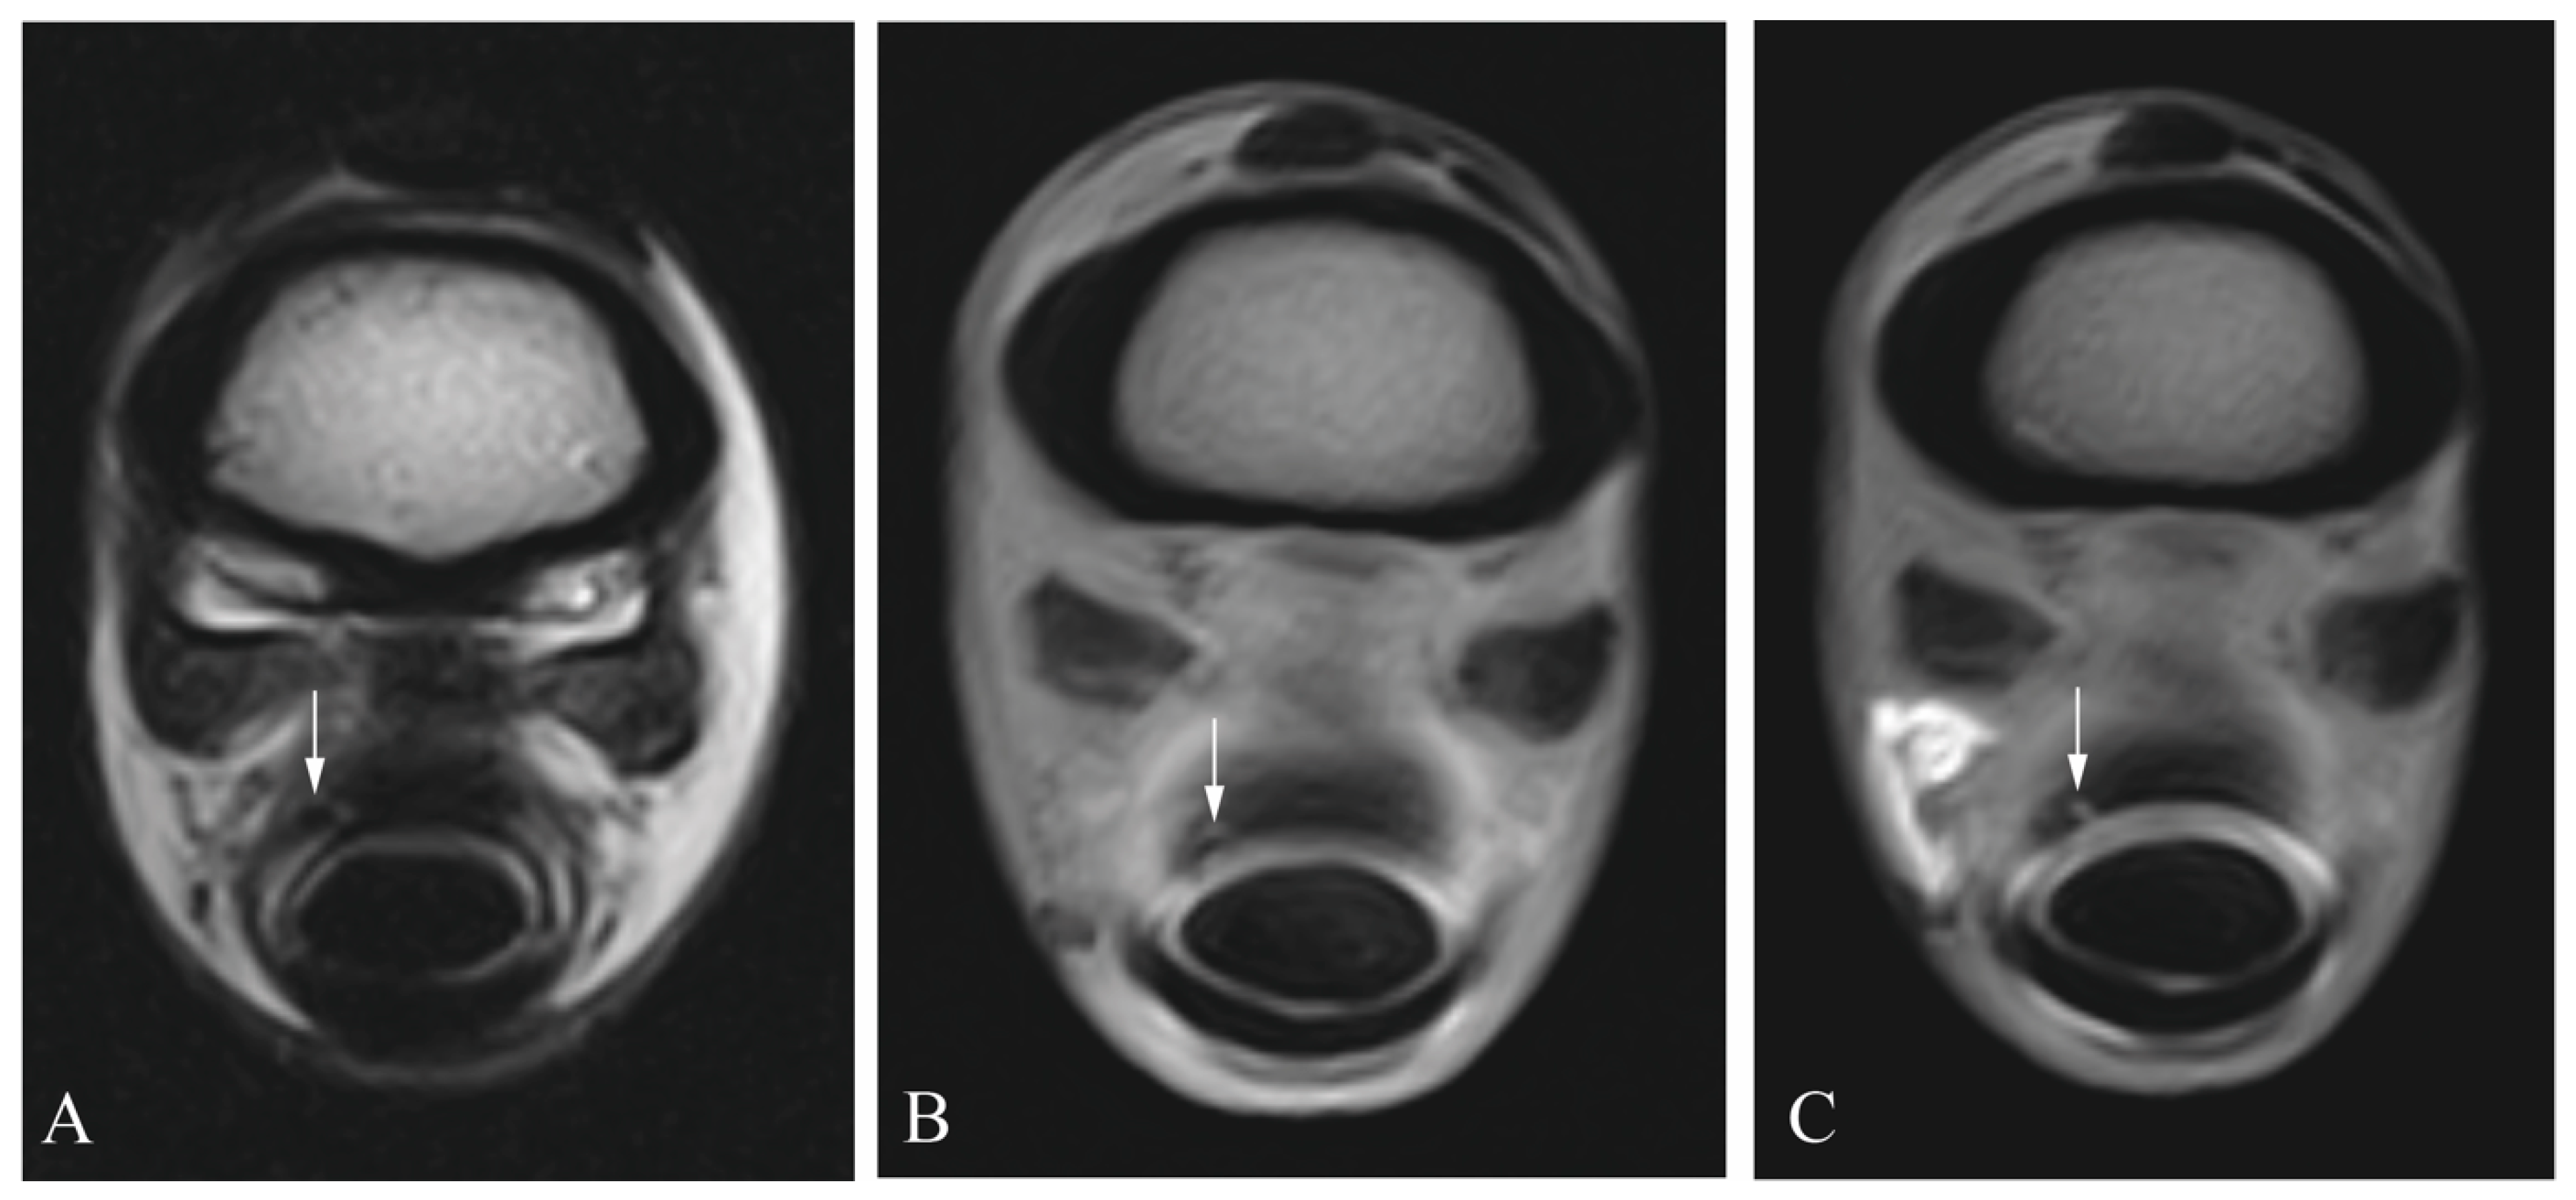

2.3. Diagnostic Imaging

2.4. Image Analysis